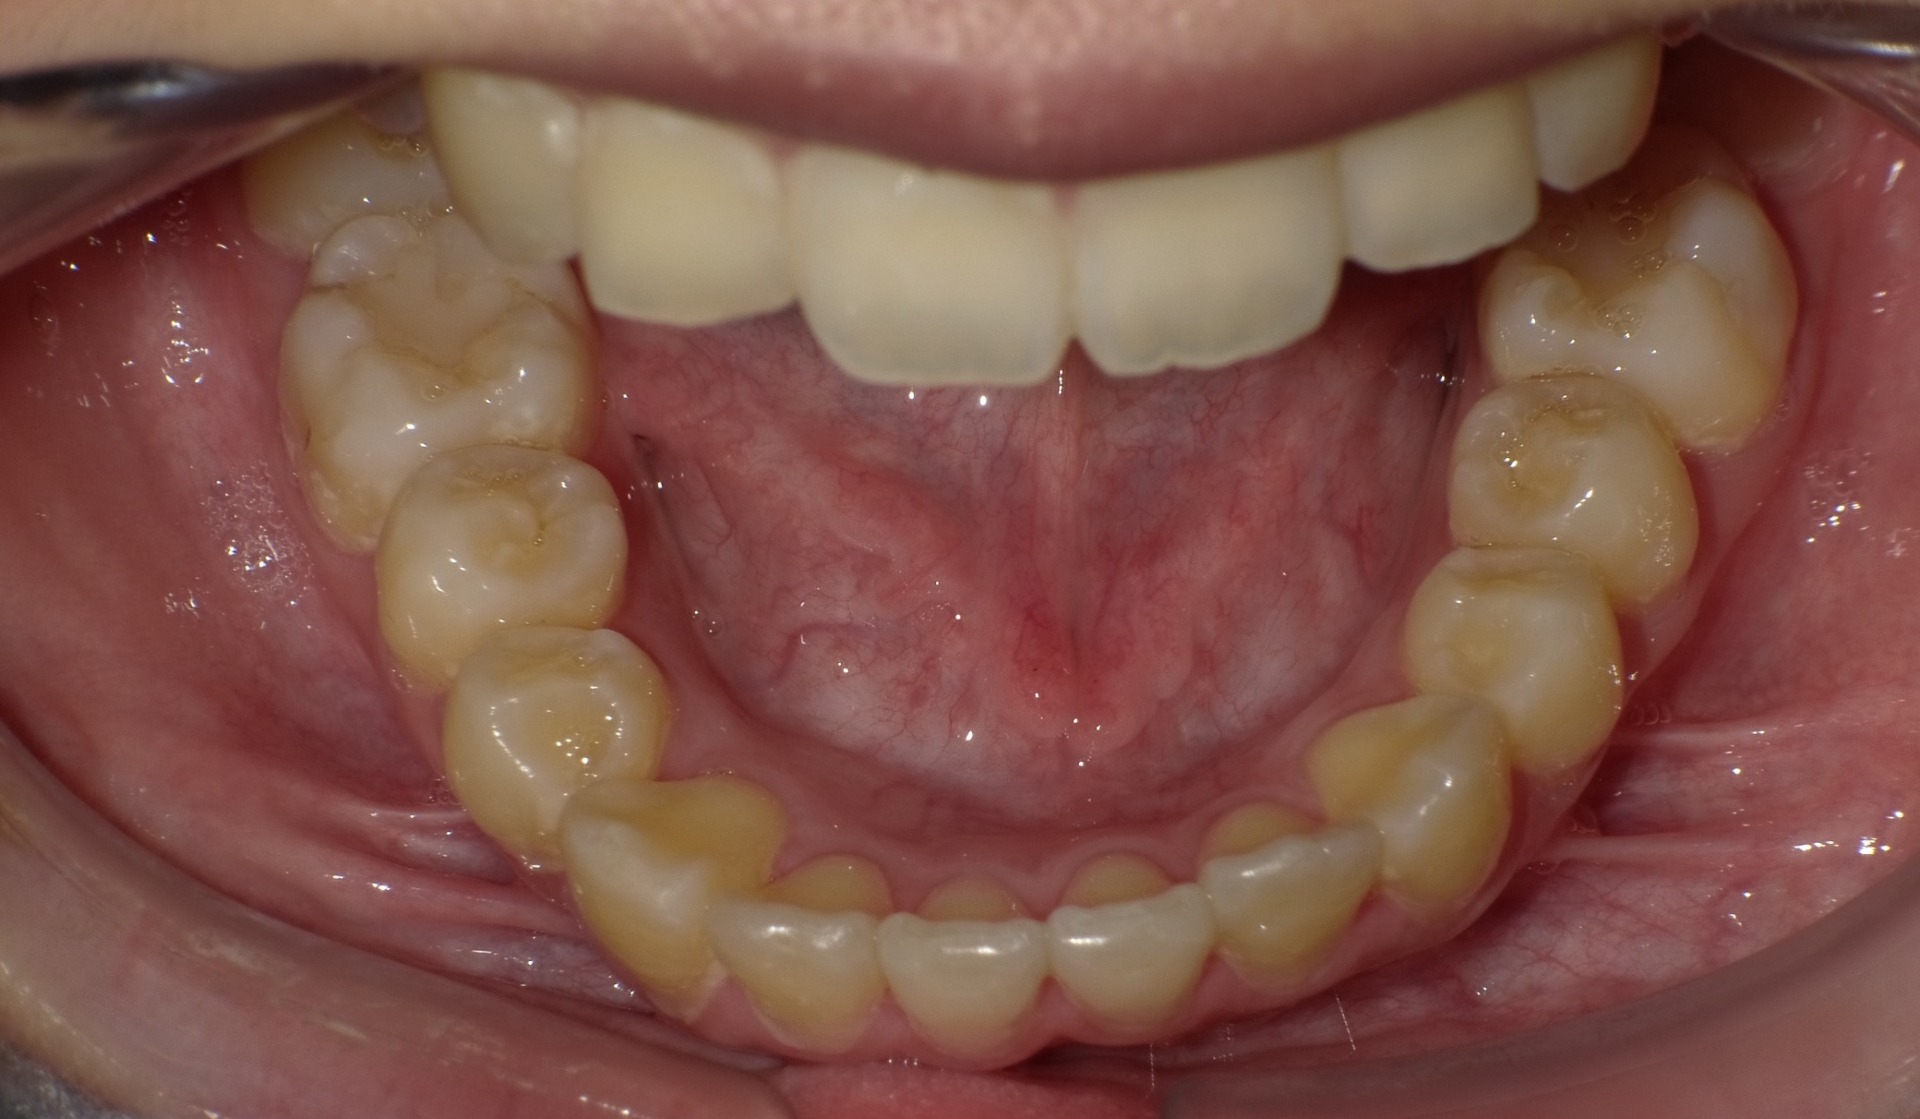

症例1-②

そして、永久歯がすべて生えそろって症例1-②の写真のようになります。上は、軽度の八重歯です。この程度の八重歯は永久歯を抜くことなく治療可能ですが、問題は右下の4番がスペースがまったく無いということです。ここで、一般的な矯正では、右下4番の小臼歯の抜歯と、それに伴う、その他3本の小臼歯の、計4本の永久歯の抜歯を提案されるでしょう。